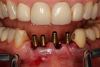

The next case follows the digital protocol for fully guided surgery and prosthetics. A CBCT radiograph, digital impression, and digital photography were the cornerstones to the success of this case. The 3D data set was electronically delivered to the dental laboratory. The data were merged and the process to develop the plan was initiated. The use of CBCT was essential in this case, particularly due to minimal space for placement of individual implants and single-unit crowns. The patient's chief concern was that she wanted to have single-unit crowns instead of fixed crown-and-bridge restorations because she was worried that she would someday find herself in an assisted-living facility; if that were to happen, she wondered, who would help floss under her bridge work? Her decision was to have single implants with individual crowns. CBCT technology is much more accurate in evaluating space maintenance and management.10 Periapicals in the past were rather close for calculating spacing; however, the CBCT identifies the buccal-lingual dimensions as well as the mesial-distal measurements. On review of the completed proposals for implant placement and provisionals, it was determined that there was sufficient spacing for implant placement to allow appropriate emergence profiles for the provisionals and then eventually the final single-unit cemented crowns. The proposal was accepted, and a 3D-printed surgical stent was fabricated, along with the PMMA provisionals (Figure 29 through Figure 35).

Fig 36. Anterior central view.

Figure 36

Fig 37. Pontic removal of No. 23 and teeth extractions.

Figure 37

Fig 38. Periodontal casualties.

Figure 38

Fig 39. Surgical guide in place.

Figure 39